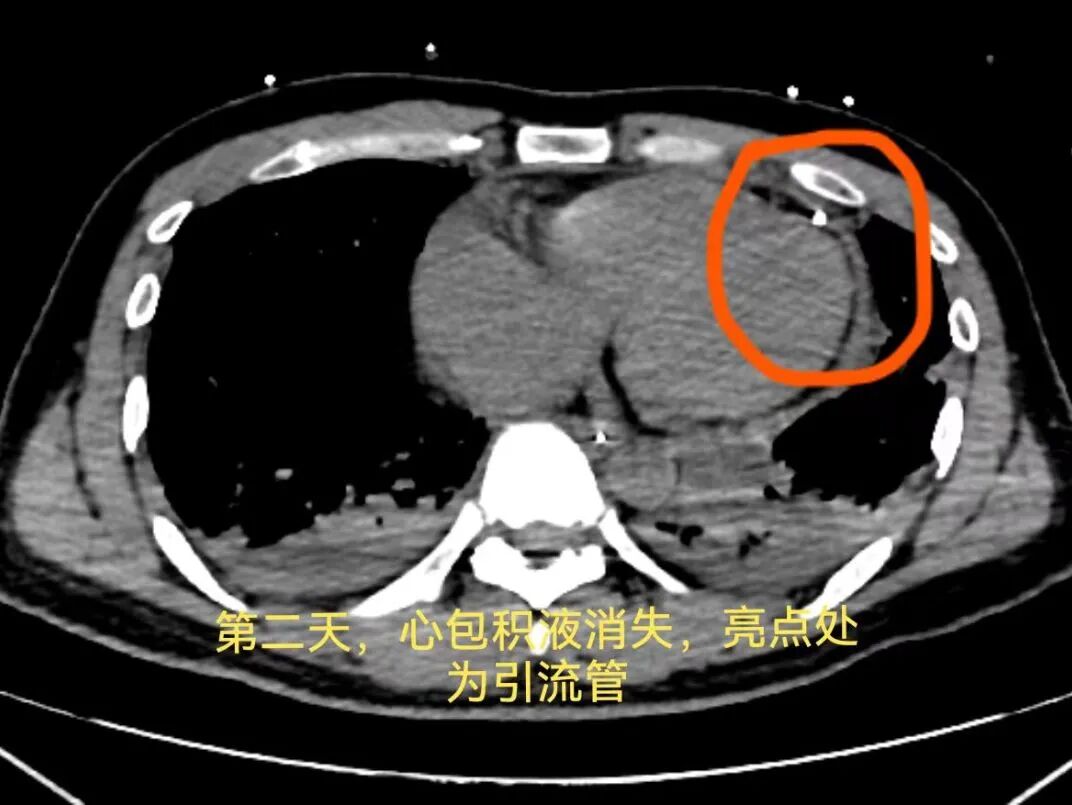

当 40 ml 血性不凝固积液被迅速抽出的瞬间,患者血压开始稳步回升;引流积液量达到 80 ml 左右时,患者血压恢复正常,意识也彻底清醒过来。

随后,患者被转入重症监护室进一步观察治疗。在医护团队的精心照料下,生命体征持续稳定,仅用 4 天便顺利转出 ICU,返回胸外科普通病房。转回病房次日,患者成功拔除心包引流管,痊愈出院,重归正常生活。